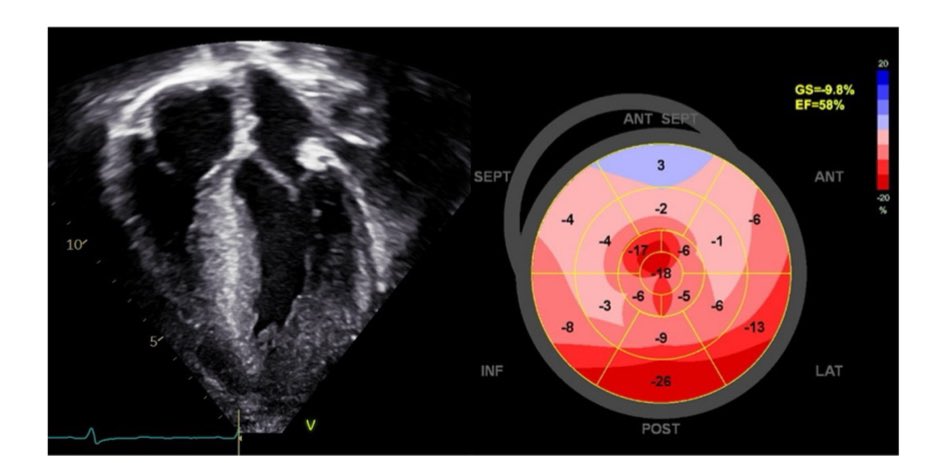

Non-compaction kardiomyopati. Hva er det og er det egentlig en egen entitet? Lær mer i denne grundige gjennomgangen av #NinaHasselberg @ProCardio1 https://t.co/gqjT4WguGF